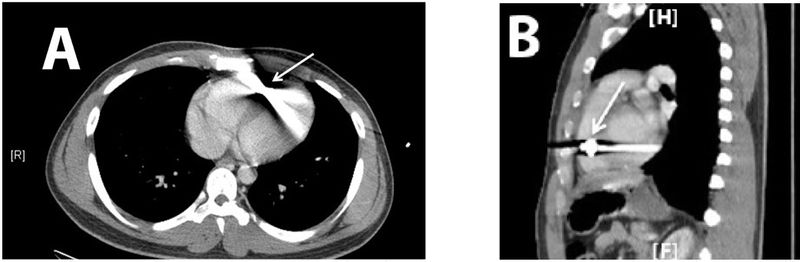

| current | 15:59, 2 August 2016 | 1,040 × 341 (70 KB) | Agarispe (Talk | contribs) | <ref name="litreview"> Lu, K., Gandhi, S., Qureshi, M., Wright, A., Kantathut, N., & Noeller, T. (2015). Approach to Management of Intravascular Missile Emboli: Review of the Literature and Case Report. Western Journal of Emergency Medicine, 16(4), 489–496. http://doi.org/10.5811/westjem.2015.5.25553 </ref>: |